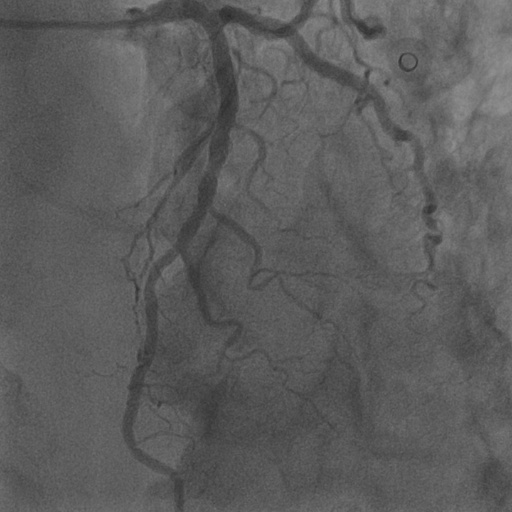

4.1 XACV Dataset

We collect 111 complete records of coronary artery X-ray videos from 59 patients, encompassing the injection, flow through the blood vessels around the heart, and dissipation of the contrast agent. Subsequently, we establish the XACV (X-ray Angiography Coronary Video) dataset. Each video consists of an average of 86 frames of high-resolution coronary artery X-ray images, with an equal distribution of left and right coronary arteries. We invite experienced radiologists to annotate the vascular regions, focusing on one or two frames where the contrast agent is most prominent in each video. These annotations are used only for evaluation in our method, not for training, maintaining the unsupervised nature of our approach. The data collection protocol involves several key steps, including patient preparation with informed consent and metal object removal, image capture using a Philips Allura Xper FD20 machine for standardized frontal (PA) and lateral views, DICOM file storage, and de-identification for patient privacy. Experienced radiologists perform diagnostic annotations using standardized tools and methods, with multiple annotations to enhance accuracy. Quality control measures, secure data management, and strict adherence to ethical guidelines and privacy regulations are implemented throughout the process. The XCAD dataset contains only a single image, and the CADICA video dataset does not provide corresponding ground truth. Therefore, in the following experiments, we conduct all the analyses on our collected XACV dataset and the corresponding GT for each sequence. In Figure 5, we show that compared to other publicly available datasets, XCAD (Ma et al., 2021) and CADICA (Jiménez-Partinen et al., 2024), our dataset exhibits finer annotations in the vascular regions, providing an advantage for future related tasks. The development and use of our dataset have been approved by our institution’s IRB. We will make the XACV dataset publicly available.